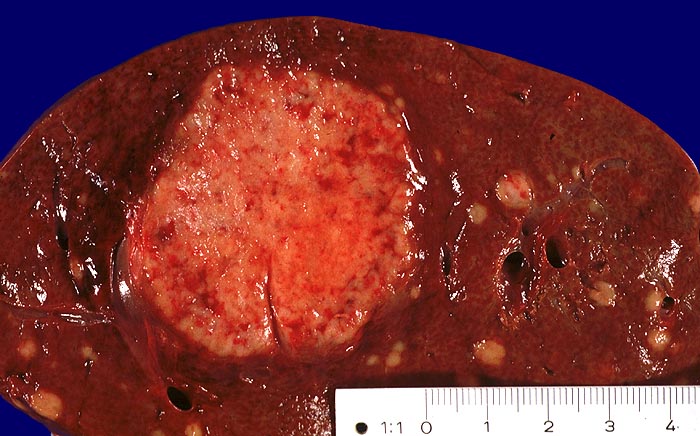

PathoPic ID 1368 - Metastase neuroendokrines Karzinom

Metastase neuroendokrines Karzinom

maligner Tumor

Leber

Leber, Gallenwege, Pankreas

Multiple runde Metastasen.

Makroskopie